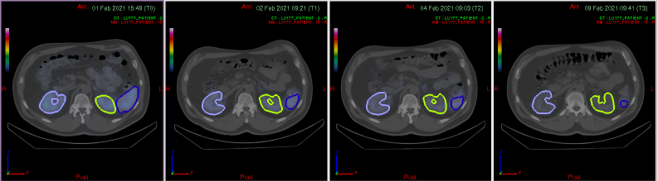

SPECT/CT showing 4 time points

Organ segmentation and TAC fitting from reconstructed SPECT/CT

TIAC/AUC analysis — organ-level (OLINDA/EXM) and voxel-based (PLANET® Dose)

Absorbed dose (Gy) — organ, tumour, bone marrow